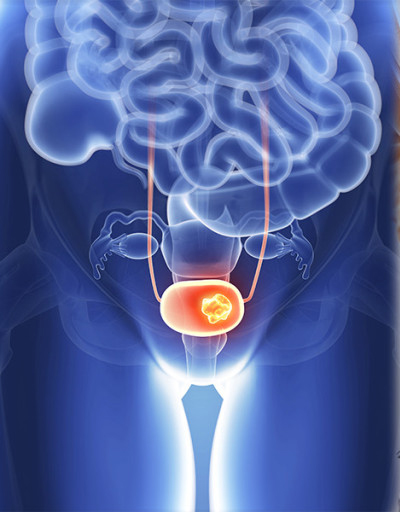

전립선암은 주로 전립선의 바깥쪽 부분인 말초대(Peripheral Zone)에서 발생합니다. 이 때문에 종양이 요도를 압박할 정도로 커지기 전까지는 증상이 나타나지 않는 경우가 많지만, 아래와 같은 비뇨기계 증상 및 전신 증상이 나타나기 시작하면 반드시 정밀 검사가 필요합니다.

- 혈뇨 (소변에 피가 섞임)

- 설명: 암이 요도 주변이나 방광 쪽으로 침범하거나 전립선 내에서 출혈이 발생하면 소변에 피가 섞여 나오는 혈뇨가 발생할 수 있습니다. 혈뇨는 전립선암 외에도 방광암, 신장 질환 등 다양한 원인으로 발생할 수 있으므로, 육안으로 피가 보이거나 소변 검사에서 혈뇨가 확인되면 즉시 정밀 검사가 필요합니다.